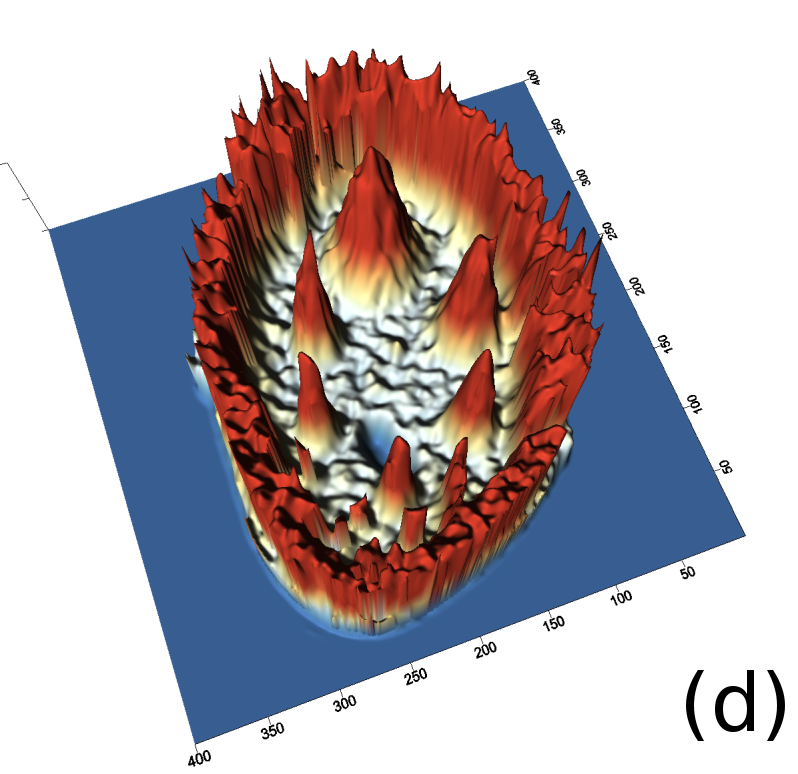

Reconstructed images are presented in Fig. 4. Since CGLS-TV- reconstruction might look more appealing than CGLS-EL we also show the surface representations of reconstructed images (see Fig. 5) and horizontal middle cross-sections (see Fig. 6).

One can notice that CGLS reconstruction is very noisy. CGLS-TV method better suppresses noise, however smooth features are strongly affected by the “staircasing” effect. CGLS-TV- method provides reconstruction with smoother features and CGLS-EL method resolves smooth features even better (e.g. cone-shaped parabola). Although CGLS-EL method performs very well for smooth objects one can notice the wave-like variations of intensity in the background and also at the top of the rectangle (see Fig. 6). This issue can be explained by the properties of our regularizer, in contrast to TV, our penalty does not seek the sparsest solution and does not penalize strongly (pushing to the constant value) a small intensity perturbations. The EL term tends to preserve all sharp edges while uniform noise is smoothed isotropically with the Laplacian. In Fig. 6 one can see that the CGLS-EL method provides better recovery of smooth features while slightly higher (compare to TV and TV-) perturbations visible in uniform areas (the top of the rectangle), however, the edges of the rectangle are defined sharper with the EL penalty.